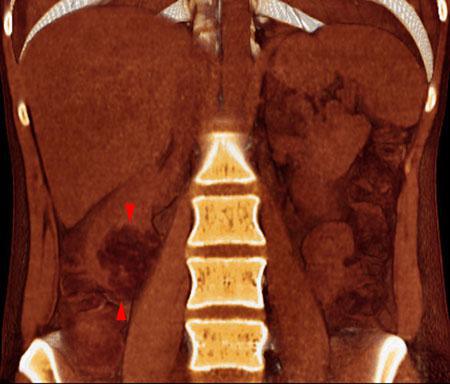

Angiomiolipoma renal 2

VR seccional. Visión coronal anterior. Estudio no contrastado que muestra una tumoración con contenido graso (puntas de flecha) en polo renal inferior derecho